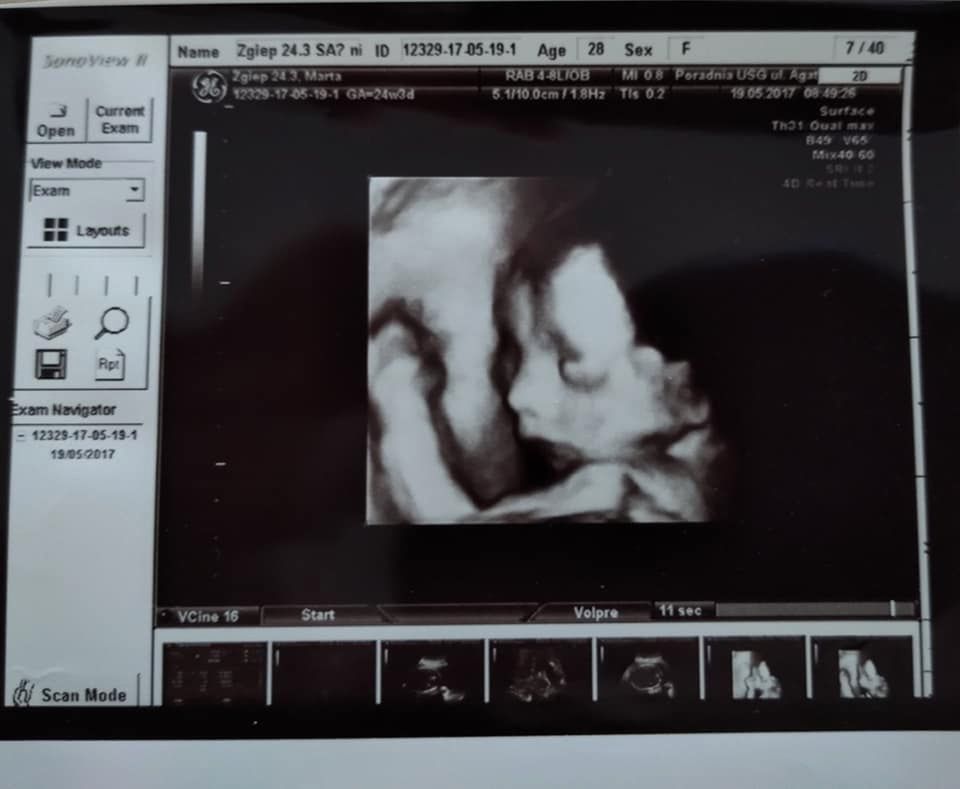

O tym, że chłopiec jest śmiertelnie chory, rodzice dowiedzieli się w 24. tygodniu ciąży.

- Diagnoza, którą usłyszeliśmy, była tragiczna, Stefcio praktycznie umierał już w tamtym momencie. Krytyczna stenoza aortalna i postępujący obrzęk - to usłyszeliśmy od lekarzy. Okazało się, że serduszko jest znacznie powiększone, Stefanek ma już obrzęki, gromadzą się płyny w brzuszku - wspomina mama.

Rodzice nie mogli w to uwierzyć, badanie USG - wykonywane zaledwie miesiąc wcześniej - nie wskazywało na żadne nieprawidłowości.

Podczas badań w ciąży okazało się, że chłopiec ma poważną wadę serca

Podczas badań w ciąży okazało się, że chłopiec ma poważną wadę serca © arch. prywatne